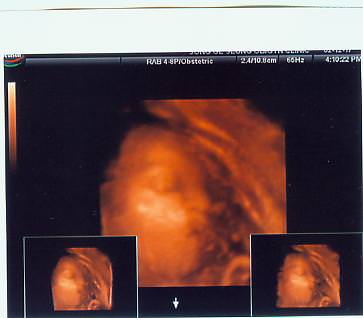

우리가족사진 찰칵!

아래는..사진콘테스트 본선에 진출했던..

하니군의 사진앞에서^^